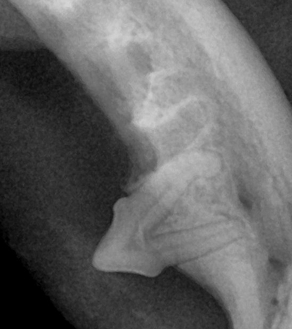

< 치아 단면구조 >